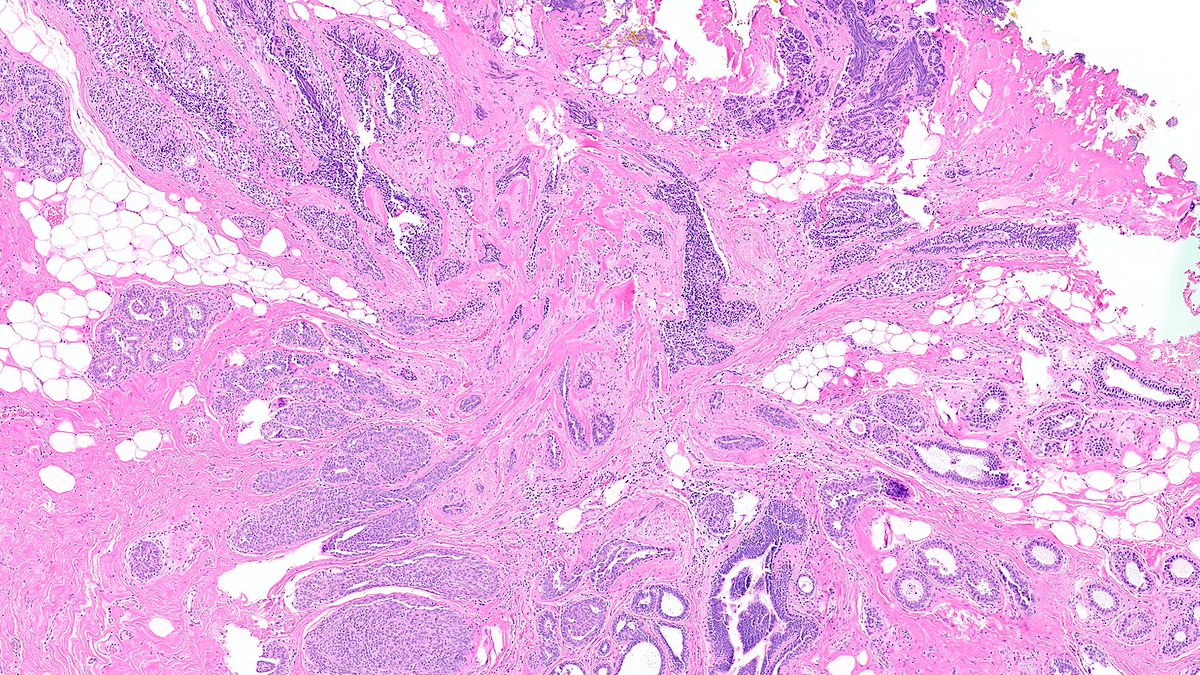

Burkitt lymphoma in action, completely involving one lymph node and crossing into an adjacent lymph node with a normal architecture #Hemepath #Lymsm #PathX #PathTwitter #Surgpath #MedEd

SibaElHussein's tweet image. Burkitt lymphoma in action, completely involving one lymph node and crossing into an adjacent lymph node with a normal architecture #Hemepath #Lymsm #PathX #PathTwitter #Surgpath #MedEd